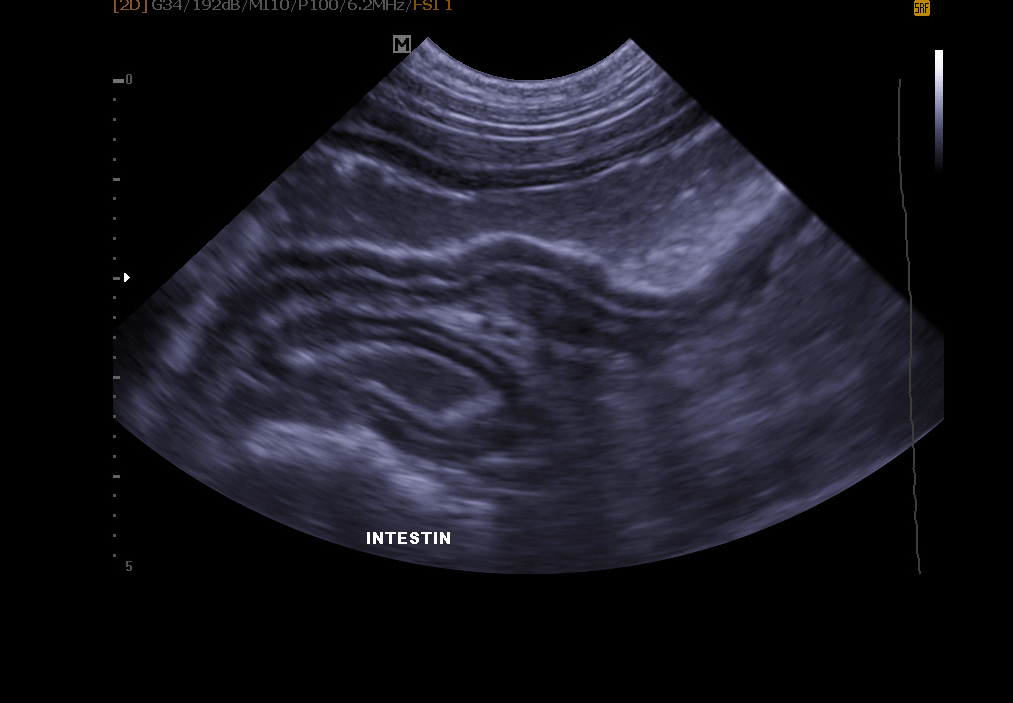

Abdomen-Ultraschall: ermöglicht die Untersuchung der Blase (Suche nach Steinen, Polypen, Tumor), Nieren, Milz, Leber, Bauchspeicheldrüse und anderen Bauchorganen.